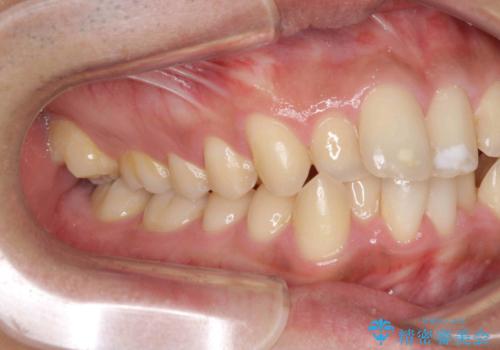

歯を抜かない矯正 奥歯のすれ違い咬合 下の八重歯

- 前歯のガタガタを主訴に来院。

奥歯はすれ違ってしまっていました。

口元も出ておらず、非抜歯を希望されたため、IPR(歯を削る処置)でスペースを確保しました。

上顎両側7番(一番奥の歯)はすれ違っており、虫歯になっていました。